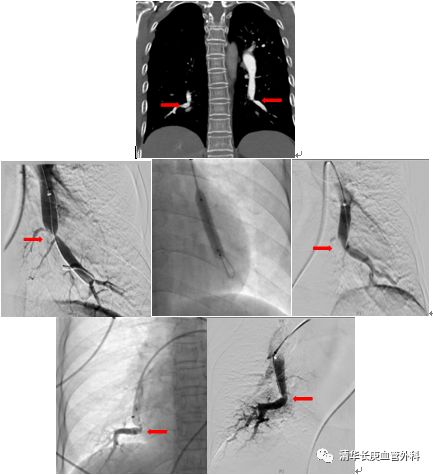

北京清华长庚医院血管外科团队在吴巍巍主任的带领下,联合多科讨论后决定采用肺动脉球囊扩张成形术治疗通过右侧股静脉入路,选择进入患者左侧肺动脉基底段狭窄部位,完成肺动脉球囊成形术,球囊扩张后肺动脉形态改善。患者术后在监护病房观察一天后顺利返回普通病房,患者恢复顺利。一周后再次行右侧肺动脉基底段球囊扩张。患者术后6分钟步行距离明显提高,术后2天即可行走450m,肺动脉压力由术前82mmHg降至8mmHg6 。患者顺利出院,由于双侧肺动脉病变广泛,此后还将密切随诊,择期再次行其余部位的肺动脉腔内治疗。

双侧肺动脉基地段狭窄,球囊扩张前后对比